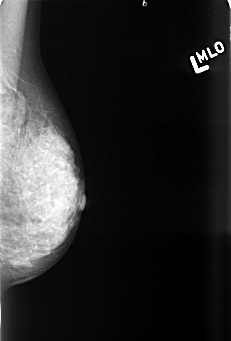

B_3437_1.LEFT_MLO

LEFT_MLO LINES 4424 PIXELS_PER_LINE 2992 BITS_PER_PIXEL 12 RESOLUTION 50 NON_OVERLAY